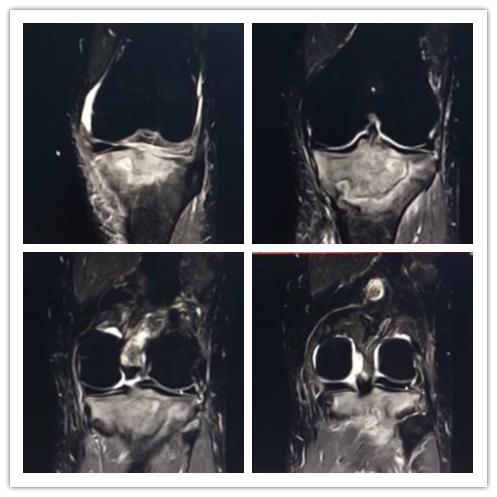

白血病关节病变:周某,男,71岁,既往白血病史,膝关节疼痛一月。

【eT2-TSE COR CLEAR 】

影像所见:

关节腔及髌上囊见少量积液,左股骨下段及胫腓骨上段见片状异常影,边界尚清,呈地图形,T2WI呈稍低信号影。

【eT2W-SPAIR COR】

脂肪抑制序列胫骨上端见片状高信号影,信号不均。

【ePDW-TSE COR CLEAR】

内、外侧半月板前后角形态及信号正常,边缘规整,前后交叉韧带、内外侧副韧带及髌韧带形态及信号未见异常。